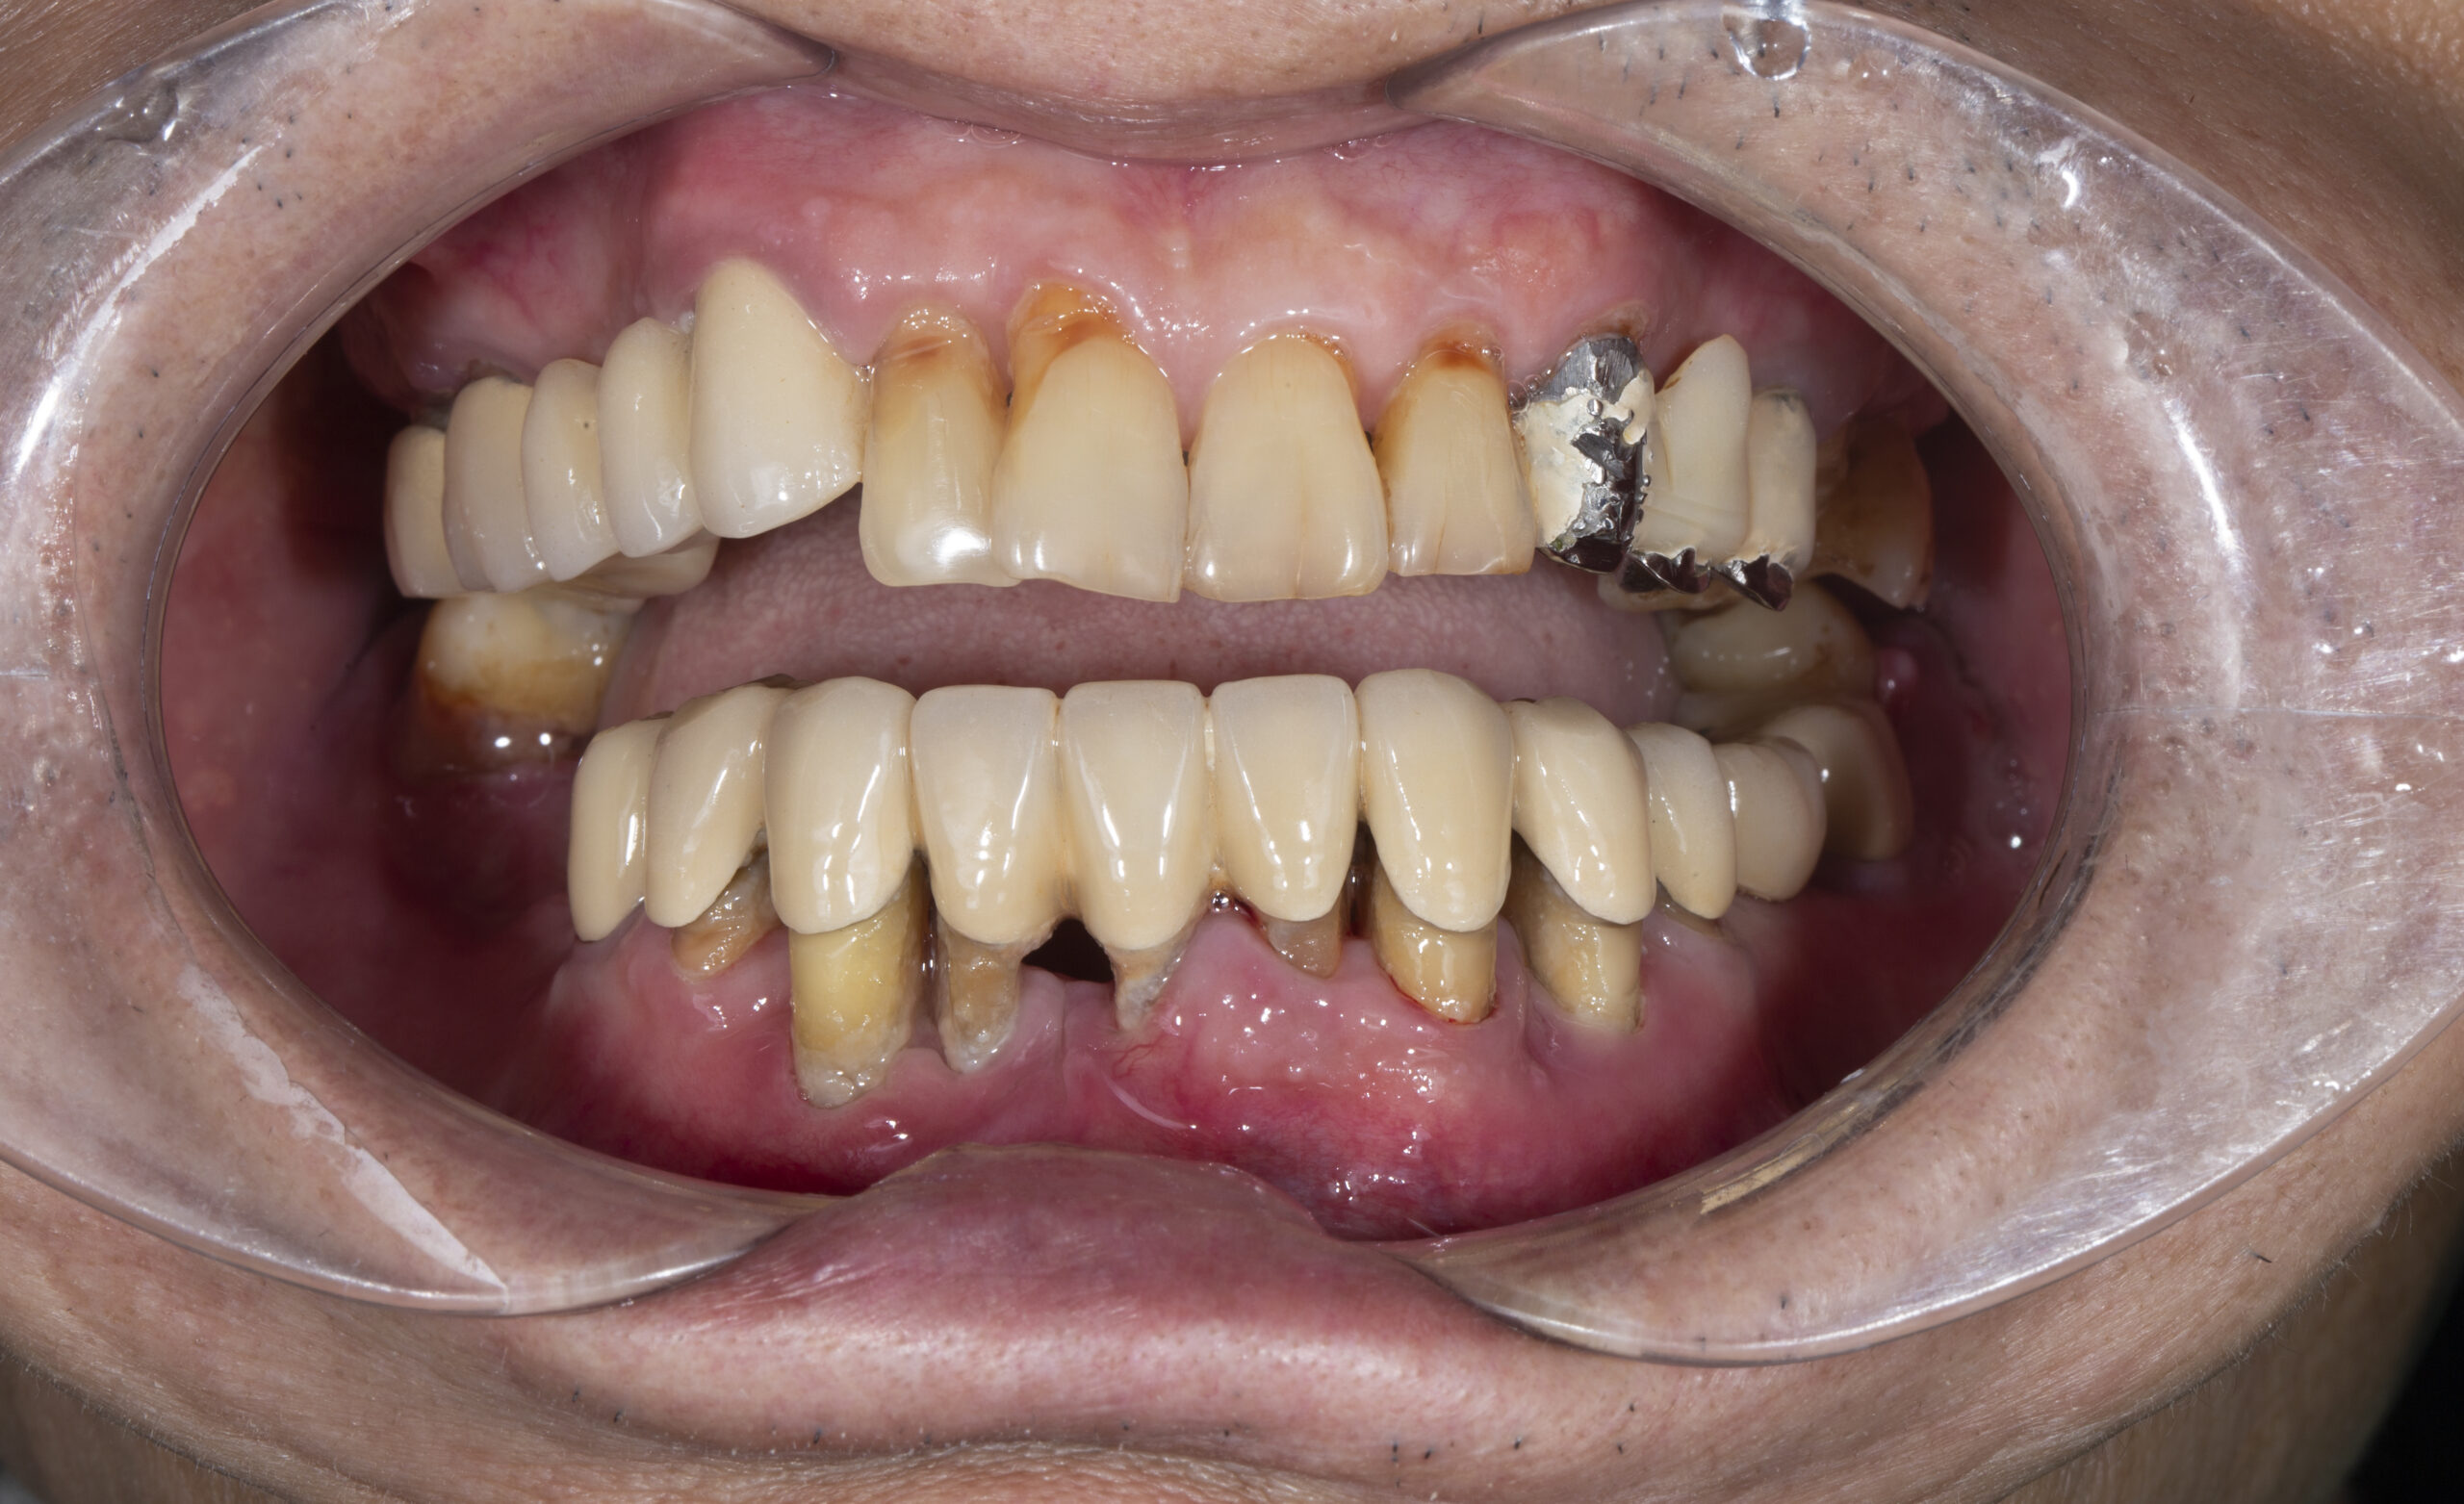

Khách hàng làm cầu răng sứ cách đây 10 năm nhưng dùng gãy, vỡ không thể ăn được

Không cần mài thêm răng thật – lợi ích vượt trội của Implant